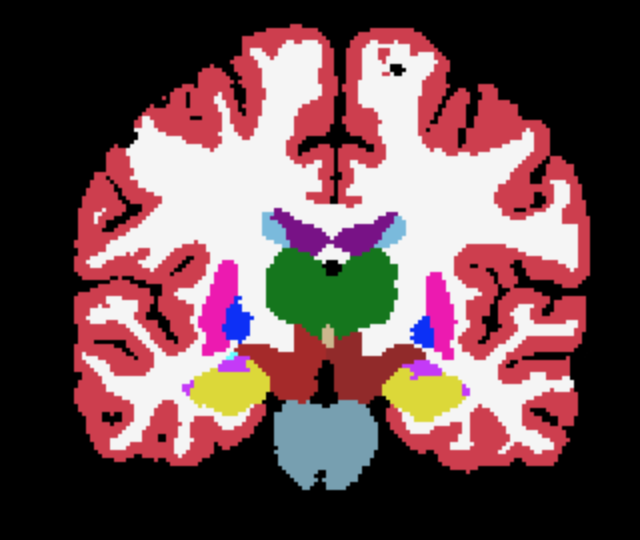

where and are the ground-truth and transformed segmentations respectively, and the Dice loss is now computed over multiple neuroanatomical structures (see Figure 1 for an example segmentation).

The overall training framework of the network is illustrated in Figure 1. Given an input scan, the network regresses both the coordinate means and the standard deviations , as well as a foreground mask . The optional atlas segmentation loss is denoted by the dashed box.

Third-level uncertainty: uncertainty at downstream tasks. To illustrate how the uncertainty could be used in a downstream task we show samples of atlas deformations and associated propagated segmentations in Figures 5 and 6. Both figures highlight the variability of the samples, which would have a direct effect on any downstream analysis using quantities extracted from the segmentations, e.g., regional volume (Desikan et al., 2009). The sample-to-sample differences, along with the variance, are again concentrated on the cortex. This registration-based uncertainty, when not accounted for, can decrease the power of downstream statistical analyses, or be mistaken for aging effects if the registration errors correlate with age.